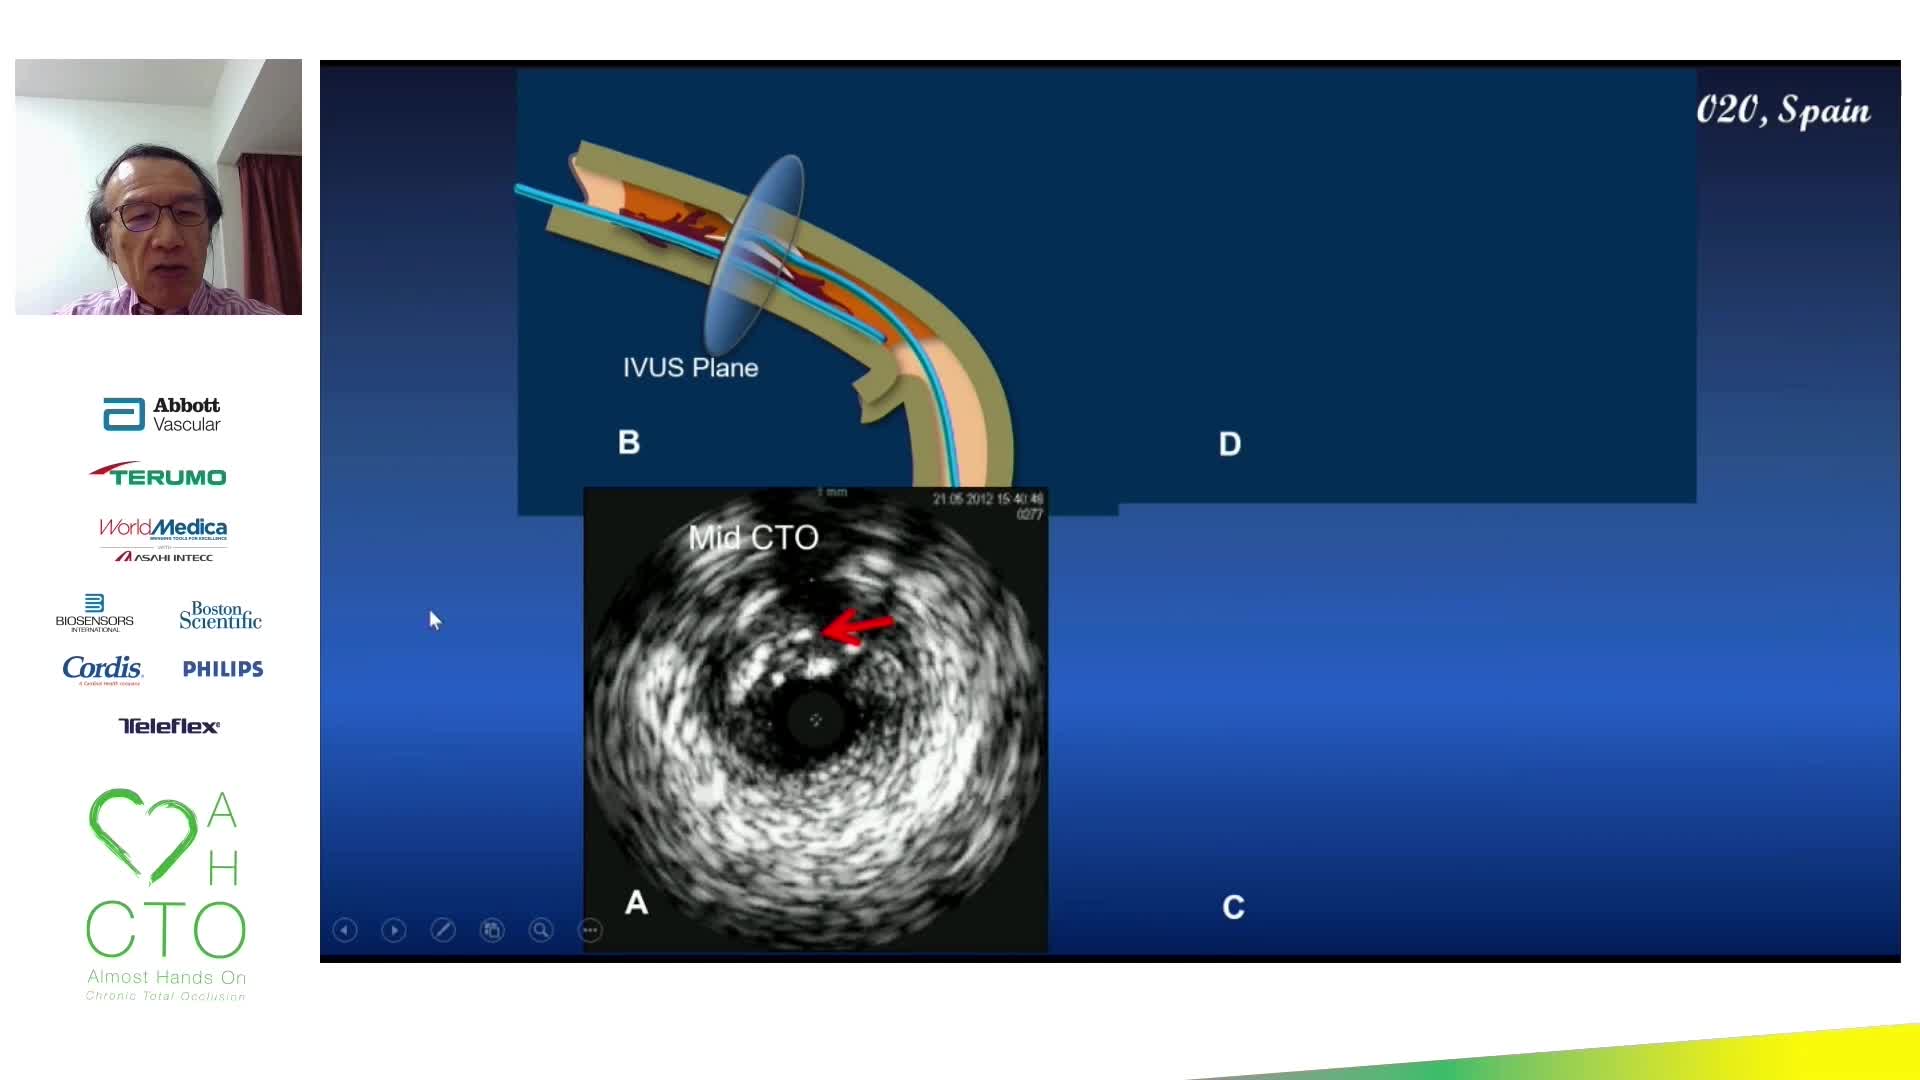

12th AHO meeting December 2020

Evidence base for IVUS: to support use in routine practice - Prof Erick Schampaert